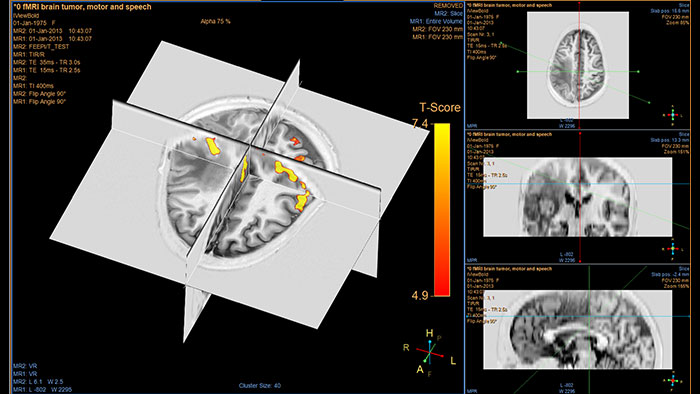

Comprehensive reviewing tool for multiple modalities, all in a single viewer

Getting a full picture of your patient imaging status, begins with reviewing and analyzing images from multiple modalities in a single viewing environment. Quantify and measure disease states using multiple 3D tools as well as data from CT, MR, and other modalities (e.g. NM, DXR, US).

Benefits